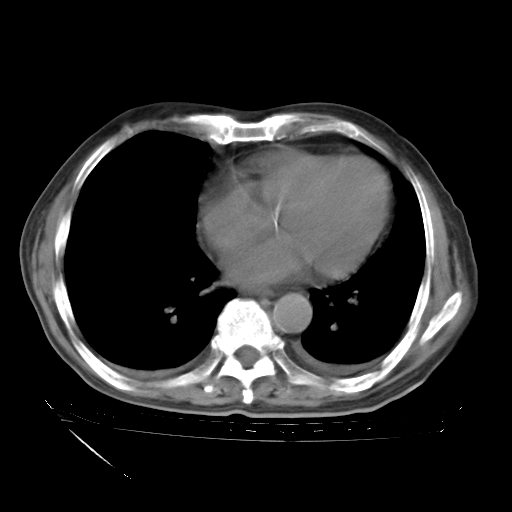

甲强龙80mg/日+抗结核治疗(异烟肼+利福霉素+乙胺丁醇)10天。复查肺部CT。

治疗10天肺部CT